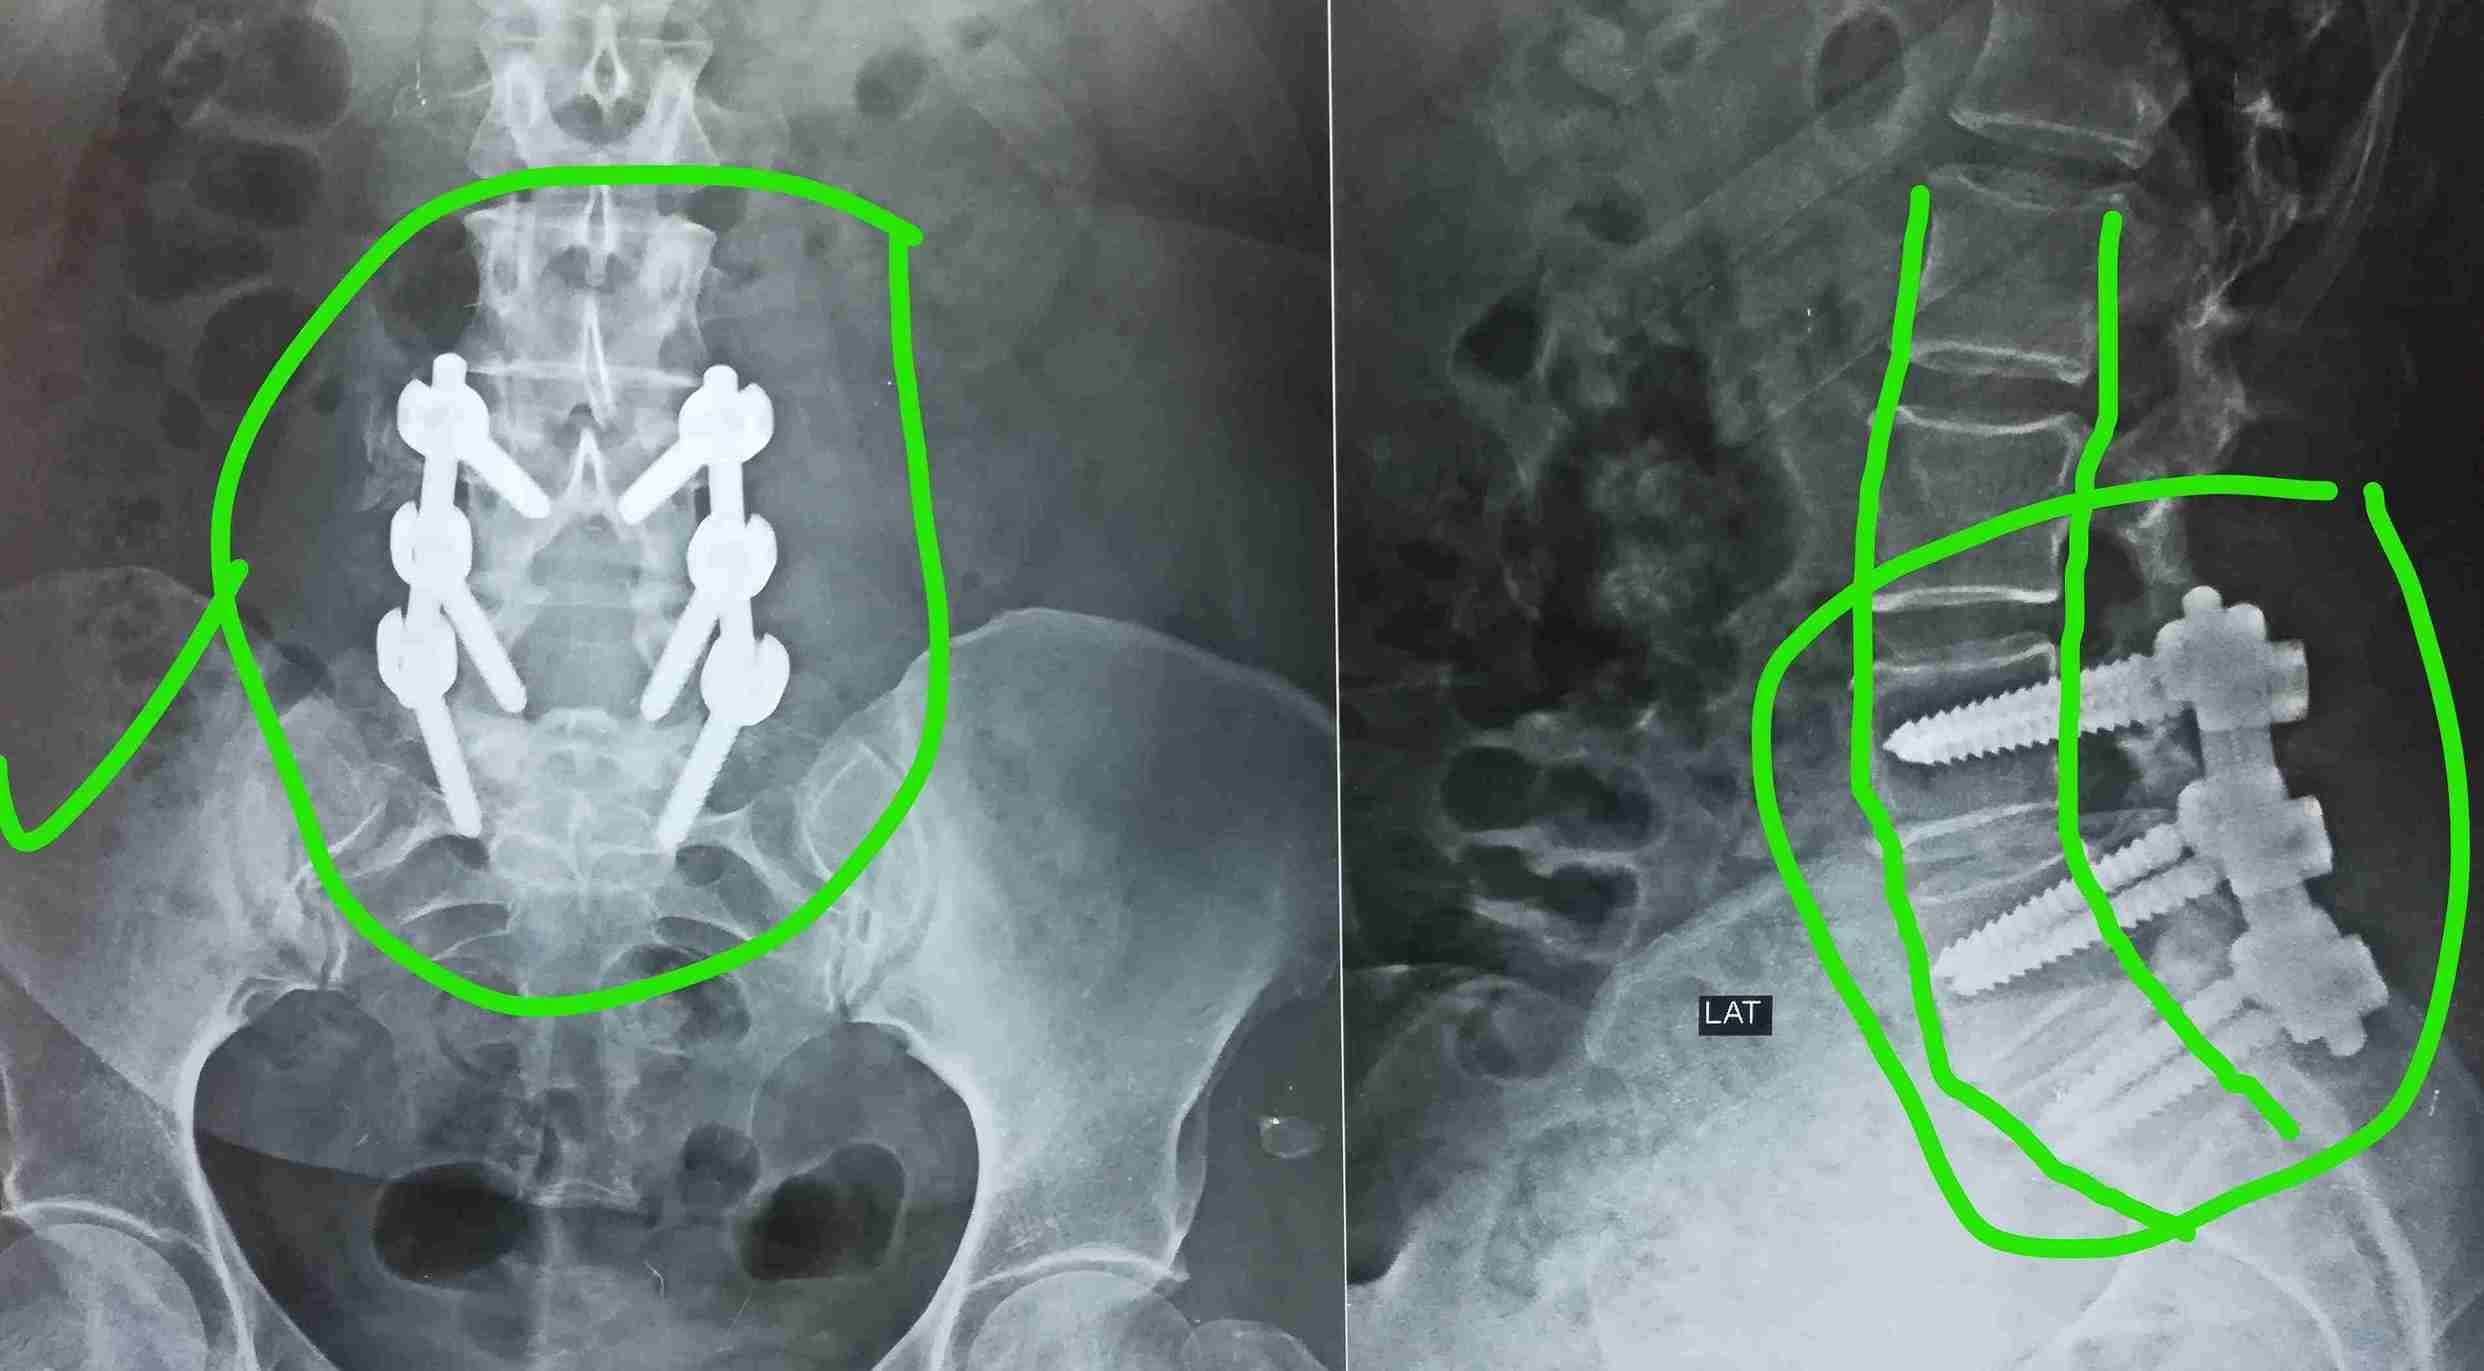

انزلاق غضروفي مع تزحزح فقاري

herniated disc with spondylolisthesis

A successful surgery was performed to treat a herniated disc accompanied by spondylolisthesis. This condition causes severe back and leg pain due to pressure on spinal nerves, significantly affecting the patient's mobility and walking ability.

• Stabilizing slipped vertebrae in correct position

• Advanced internal spinal fixation